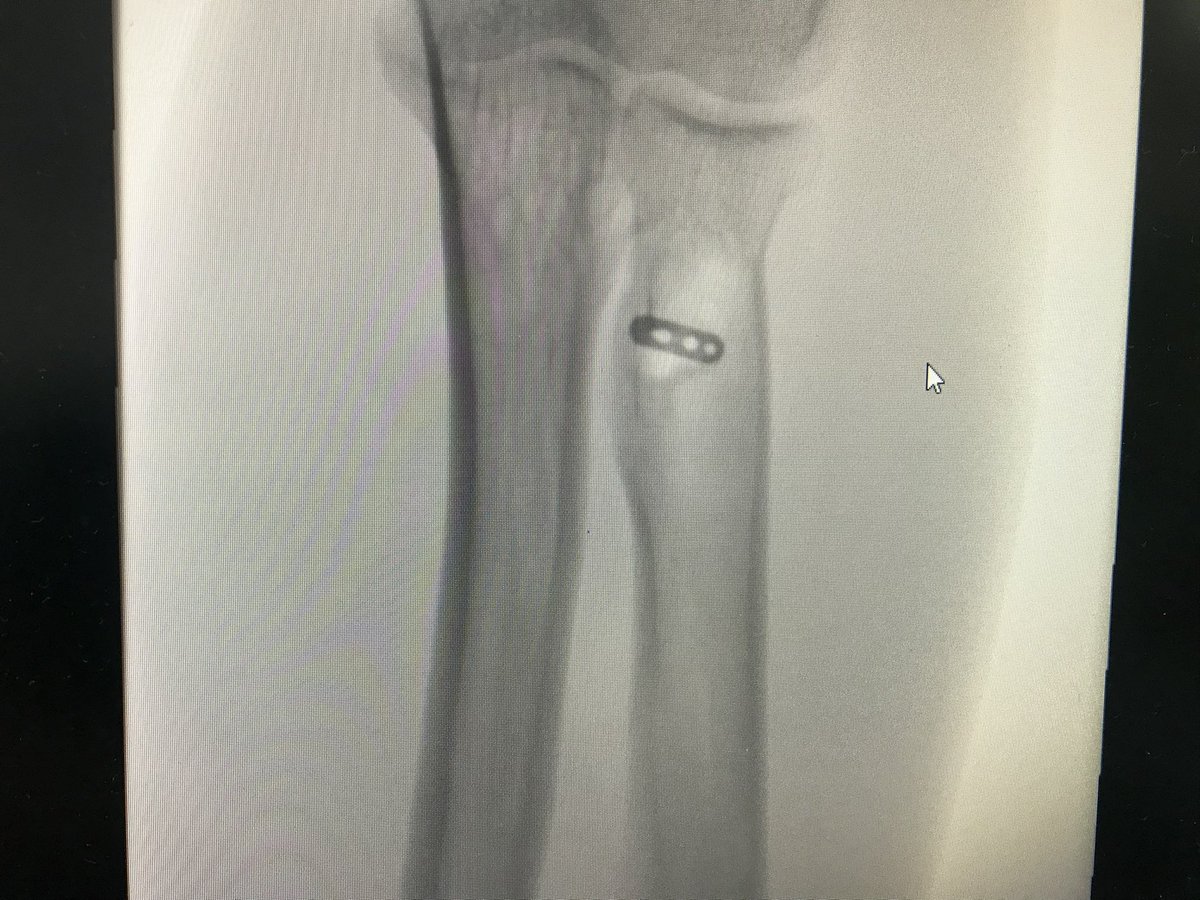

تشرفت في اخر عامين برئاسة قسم جراحة العظام في مستشفى الملك فهد بالمدينة، وكرّست عملي لـ جراحات الركبة المعقدة والإصابات الرياضية والمناظير ..